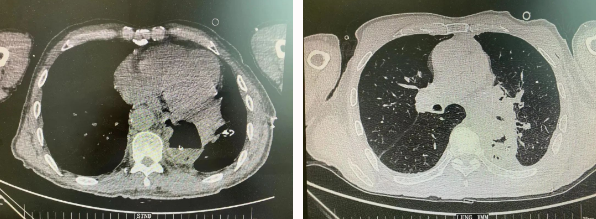

患者王某不幸同時(shí)患食管癌與左肺癌,病理類型系雙源發(fā)腫瘤,食管為鱗癌、肺為腺癌。食管癌和肺癌為胸外科最常見(jiàn)的疾病,但同時(shí)患兩種疾病,十分罕見(jiàn)。家屬輾轉(zhuǎn)多個(gè)醫(yī)院,得知李小飛院長(zhǎng)擅長(zhǎng)胸外科復(fù)雜手術(shù),慕名來(lái)西安國(guó)際醫(yī)學(xué)中心醫(yī)院。

經(jīng)過(guò)李小飛教授、李文海副教授、穆強(qiáng)副主任醫(yī)師團(tuán)隊(duì)積極準(zhǔn)備,排除手術(shù)禁忌;經(jīng)過(guò)全科術(shù)前充分討論,大家認(rèn)為:如果分兩次進(jìn)行手術(shù),另一種疾病勢(shì)必會(huì)受到影響,腫瘤可能進(jìn)展。胸外科手術(shù)對(duì)呼吸循環(huán)影響較大,同期實(shí)施兩個(gè)手術(shù)更要小心謹(jǐn)慎。李小飛教授主持術(shù)前討論,設(shè)計(jì)合理手術(shù)方式,由于食管癌胸腔鏡手術(shù)為右側(cè)入路,但為兼顧左肺癌手術(shù),則采用傳統(tǒng)左開(kāi)胸手術(shù)。

2022年4月25日,由李小飛教授主刀,同期行左側(cè)開(kāi)胸:食管癌根治術(shù) 左肺癌根治術(shù),一次手術(shù)同時(shí)根治兩種惡性腫瘤疾病。經(jīng)過(guò)精細(xì)手術(shù)及術(shù)后管理,患者術(shù)后十天,恢復(fù)良好,進(jìn)食良好,現(xiàn)已出院。